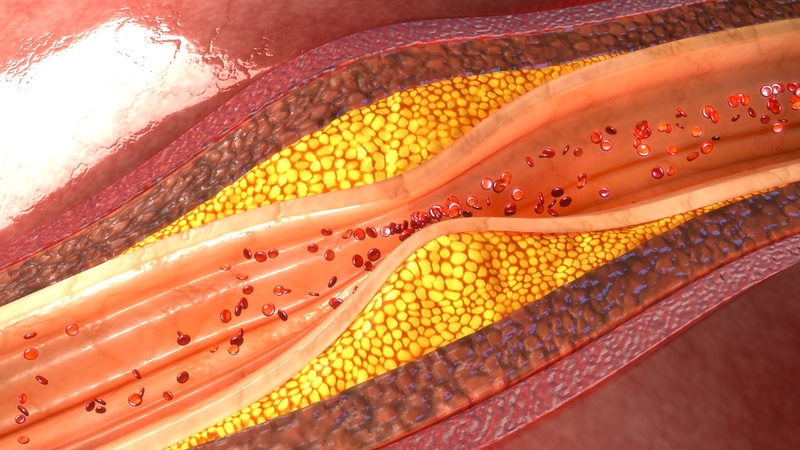

Peripheral Artery Disease

Peripheral artery disease, or PAD, is a medical condition in which the arteries become narrowed due to plaque buildup. When the plaque hardens, it limits blood and oxygen supply to the rest of the body. In addition to other areas of the body, PAD often affects the legs and feet, resulting in numbness to each. In these areas, the risk of infection is also increased, which can lead to gangrene and amputation if not treated in time. PAD also increases the risk of heart attack and stroke. It is important to consult a doctor immediately upon noticing any of the following symptoms: sores on feet or legs, leg pain when walking or climbing up stairs, weak pulse in legs, change in color, coldness in a foot or lower leg, and shiny skin on legs. The risk of PAD is higher for those who smoke or have high blood pressure, high cholesterol, or heart disease.